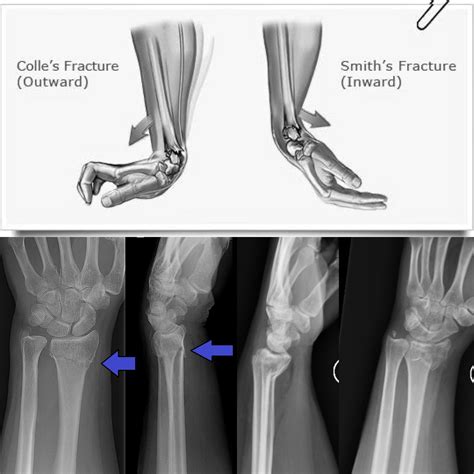

Comparing Colles Vs Smith Fracture

While both Colles and Smith fractures involve the distal radius, they have distinct characteristics that set them apart. Here is a comparison of the two:

Feature Colles Fracture Smith Fracture

Location Dorsal (back) aspect of the distal radius Volar (palm) aspect of the distal radius

Cause Fall onto an outstretched hand Fall onto the back of the hand or direct blow

Appearance "Dinner fork" deformity "Garden spade" deformity

Treatment Often non-surgical, but may require surgery for severe cases Often requires surgical intervention